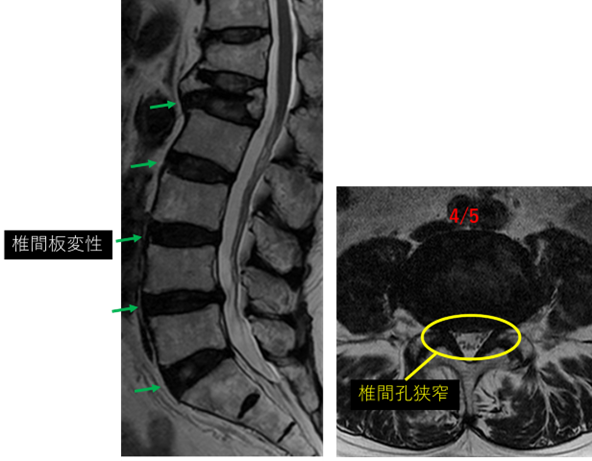

画像及び所見について

L1/2: 椎間板変性

L2/3: 椎間板変性

L3/4: 椎間板変性、膨隆

L4/5: 椎間板変性、膨隆、両椎間孔狭窄

L5/S: 椎間板変性、繊維輪断裂

以上の事が画像上認められます。

3/4、4/5、5/S に

変性、膨隆、両椎間孔狭窄 を認め、主症状の原因の可能性が高い。